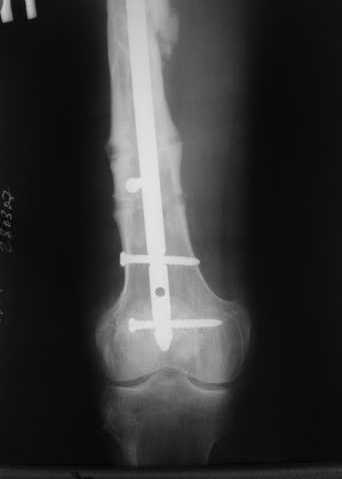

В приложении пример, дистальный отломок пружинил кзади. Два винта потому, что первый оказался чуть кпереди и не упирался в гвоздь.